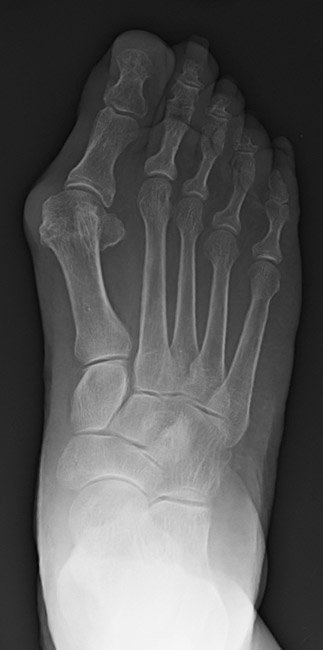

A study by Kamanii and colleagues looked at 20 people who were diagnosed with joint hypermobility syndrome according to Beighton and Bulbena score models.5,6 Comparing these people to 20 healthy controls, the researchers obtained weightbearing anteriorposterior (AP) and lateral radiographs, and assessed 11 angles. The authors found a statistically significant difference in calcaneal pitch and tarsometatarsal angles on lateral radiographs, and the first metatarsophalangeal joint (MPJ) angles on AP radiographs. From their data, the study authors suggested that people with hypermobility were predisposed to having a pes planus foot type and HAV deformities.

King and Toolan compared 15 healthy people without HAV to 25 individuals who failed conservative treatment for HAV.7 The investigators compared clinical evaluations between the two groups for hypermobility. They determined hypermobility using two methods. They assessed dorsiflexion of the first ray relative to the lesser rays with manual dorsiflexion force and subsequently assessed overloading of the second ray as determined by a plantar hyperkeratotic lesion. Researchers evaluated weightbearing AP and lateral radiographs for both groups to compare the distal metatarsal articular angle, intermetatarsal angle, MPJ angle, talonavicular coverage and the talo-first metatarsal angle. On the lateral radiographs, the study authors assessed the lateral MPJ angle, the talo-first metatarsal angle and Meary’s angle.

The authors also evaluated two new parameters for measuring hypermobility on the lateral radiographs.7 The first was the perpendicular distance between the plantar aspect of the medial cuneiform and the plantar aspect of the first metatarsal. The second technique was to measure the angle formed by the medial cuneiform and first metatarsal articular surface, extending from the superior to the inferior aspect of the joint. All the patients with HAV had clinical signs of hypermobility. In comparing patients with HAV to healthy people, the study findings revealed statistically significant differences in the distal metatarsal articular angle, the intermetatarsal angle, the MPJ angle, talonavicular coverage, the lateral talo-first metatarsal angle, the dorsal translation of the first metatarsal, the medial cuneiform/first metatarsal articular angle, and the lateral MPJ angle.

King and Toolan concluded that there was a correlation between radiographic and clinical testing for hypermobility as well as an indication for lateral imaging in determining hypermobility.7 They suggest that measurement of the dorsal translation of the first metatarsal and the medial cuneiform/first metatarsal articular angle could represent “quantifiable radiographic measures” for defining hypermobility.

From the high rate of recurrence, we can see that correction of HAV in the presence of hypermobility is not as simple as constraining the first metatarsal in space. In fact, the current thinking about the HAV deformity may not consider hypermobility as an important indicator for treatment. Dayton and colleagues state that osteotomies are mainly treating only the reduction of the intermetatarsal angle.15 They suggest that the deformity correction should take place at the center of rotation of angulation (CORA) as described by Paley and coworkers.15,16 The area of correction then would exist at the metatarsal cuneiform joint and thereby not create a secondary CORA with an osteotomy.15 Dayton and colleagues also address the frontal plane or “third plane” of the bunion deformity by derotating the first metatarsal in the frontal plane with the first tarsometatarsal arthrodesis.17 The frontal plane of deformity is visible on the sesamoidal axial radiographs as a valgus rotation of the metatarsal.

Most recently, valgus rotation of the metatarsal has become a critical element in our understanding of the cause of HAV and the role of hypermobility. Plain radiographs that show an elevated tibial sesamoid position imply that the metatarsal has migrated laterally, resulting in a bowstringing effect of the flexor tendon. However, if one considers the sesamoid position on a sesamoid axial view, it is apparent that the sesamoid remains within the sesamoid grooves in contact with the metatarsal head. Instead, the entire metatarsal rotates into a valgus position.

This brings an entirely new perspective to the term hypermobility. The rotation of the metatarsal itself gives the impression of lateral deviation of the sesamoids on the AP radiograph.15 Therefore, with triplanar correction of the bunion deformity at the metatarsal cuneiform joint, one can achieve the necessary correction at the center of rotation of angulation. By addressing the valgus rotation of the metatarsal in addition to the increased metatarsal angle and the decreased metatarsal declination angle, the metatarsal head appears to move into a more correct position. In many cases, this can eliminate the need for additional soft tissue balancing such as adductor hallucis tendon releases and lateral collateral fibular sesamoid ligament releases.15,17